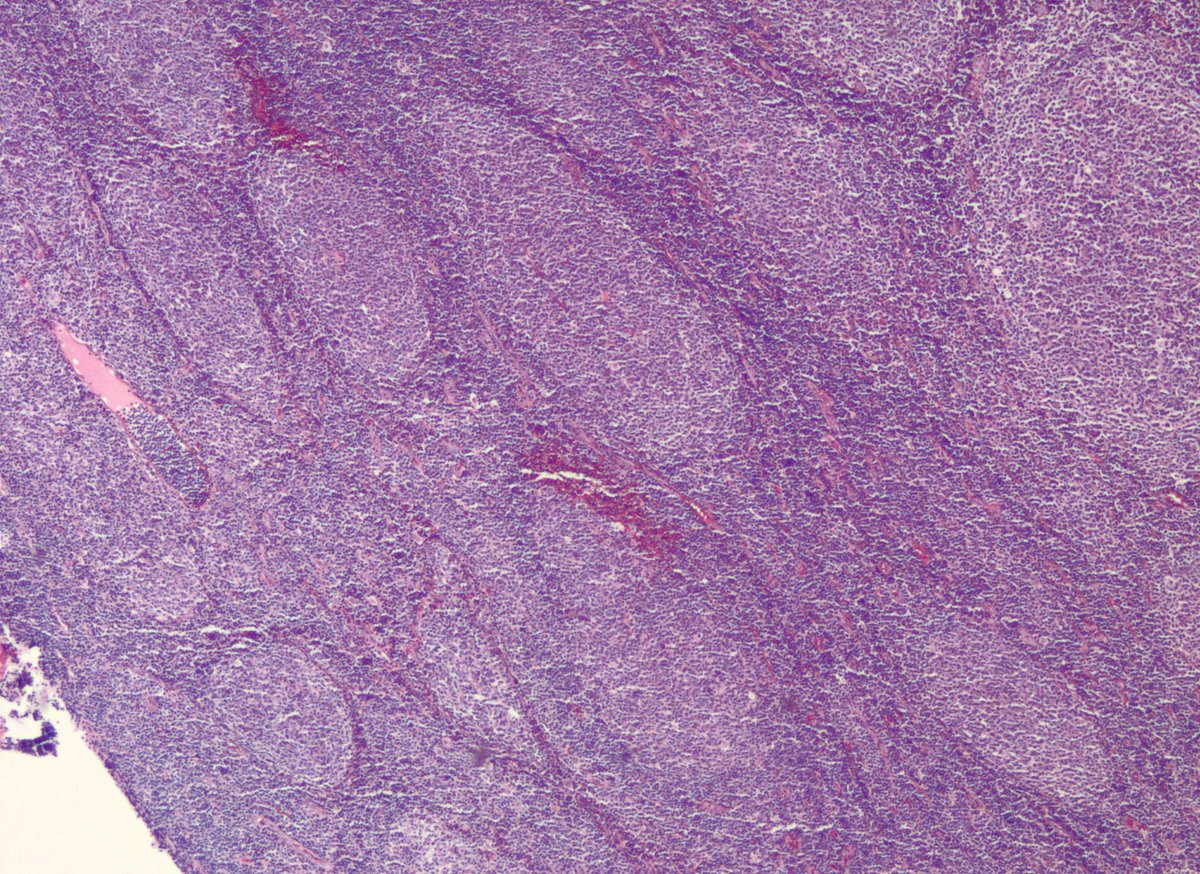

Some follicular lymphomas may appear to be BCL2-negative with commonly used IHC antibodies. Some of these cases have mutations in BCL2 that impact protein detection. Alternate BCL2 clones may be useful, as in this case. onlinelibrary.wiley.com/doi/full/10.10… #pathology #hemepath

jake_bledsoe's tweet image. Some follicular lymphomas may appear to be BCL2-negative with commonly used IHC antibodies. Some of these cases have mutations in BCL2 that impact protein detection. Alternate BCL2 clones may be useful, as in this case.